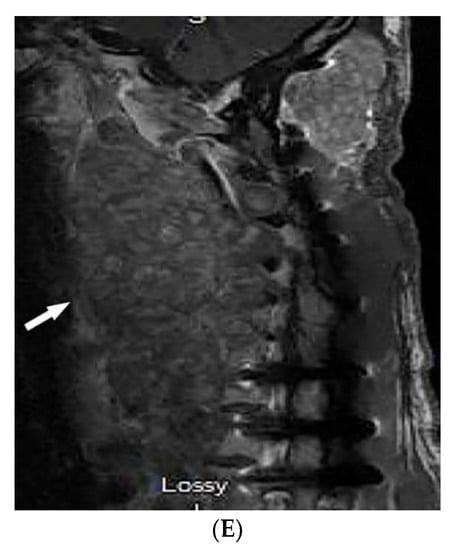

| Neurofibromatosis type 1 (NF-1) | Café-au-lait spots Freckling (axillary or inguinal) Lisch nodules Neurofibromas Optic nerve and other gliomas Skeletal abnormalities | Peripheral nerve sheath tumors including cutaneous, spinal, plexiform neuroma Diffuse thickening of the nerve |